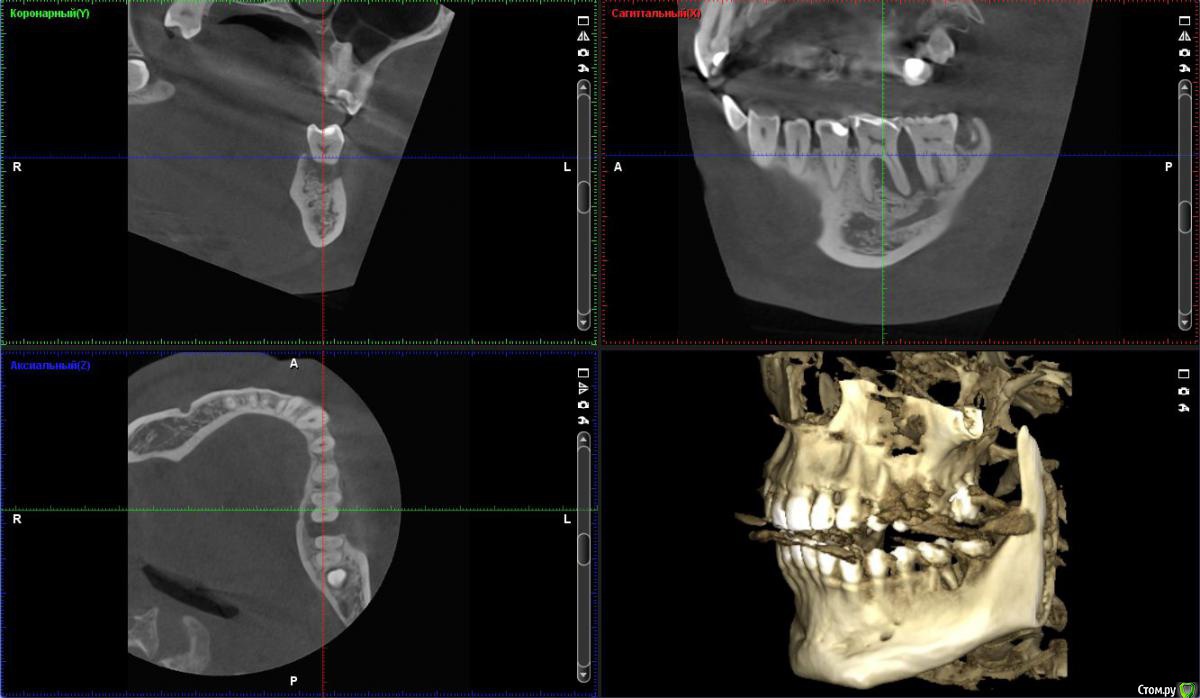

St. Опубликовано 19 февраля, 2018 Поделиться Опубликовано 19 февраля, 2018 Пациент 32лет, жалобы на боль в обл. 36-37 которую почувствовал вчера, ассиметрия лица. До этого не беспокоил никак, ни на температурные раздражители, ни на сладкое, ни на накусывание. В истории семейная предрасположенность к парадонтиту, соматически здоров.Пломбы на 36 37 нормальные, контакт есть, нависающих краев нет.Витальность не проверяли сегодня Пока хирург дал отток через карман и назначил антибиотики.Как вести дальше, какие шансы спасти 36? Ссылка на комментарий

vse32 Опубликовано 20 февраля, 2018 Поделиться Опубликовано 20 февраля, 2018 А меня больше интересует причина такого состояния. И мне кажется, что карман не первичен. Вероятно все началось периодонтитом, долгим и бессимптомным. В таком случае можно было бы попробовать эндо лечение.Но оговорюсь. Эксперимент бы проводила на родственнике - человеке перед которым нет финансовых и юридических обязательств.А так да, самое эффективное и предсказуемое лечение - удаление.Если же первичен пародонтит - то только удаление. Вот бы кто аргументированно доказал первопричину. Ссылка на комментарий

Ximera Опубликовано 21 февраля, 2018 Поделиться Опубликовано 21 февраля, 2018 Я бы тоже проверила окклюзию (супраконтакты, при боковых движениях тоже), т.к. справа ситуация с пародонтом стабильная, а слева костные карманы, причем и сверху тоже.. Ну и восьмерки, конечно( Ссылка на комментарий

Паращук Роман Опубликовано 21 февраля, 2018 Поделиться Опубликовано 21 февраля, 2018 Если свой,то попробовать эндо через временное вложение и вывести с оклюзии. Через пол-года контрольное кт. Без позитивной динамики переходить к хирургическим этапам. Ссылка на комментарий

Паращук Роман Опубликовано 21 февраля, 2018 Поделиться Опубликовано 21 февраля, 2018 + 1 к удалениюКак быть с мезиальным корнем 7ки? Ссылка на комментарий

red_butler Опубликовано 21 февраля, 2018 Поделиться Опубликовано 21 февраля, 2018 Как быть с мезиальным корнем 7ки?про седьмой и восьмой, я скромно умолчал. Надо очно смотреть. но прогноз седьмого - плохой Ссылка на комментарий